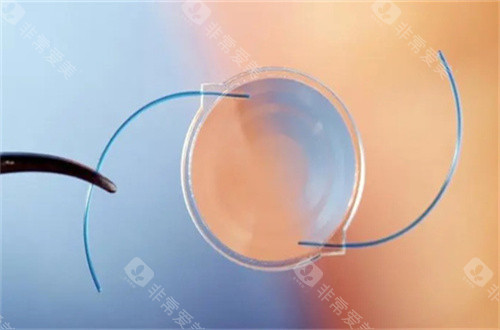

白内障正规开展了多种白内障手术,包括超声乳化白内障吸除术等,手术技术成熟,术后结果良好。